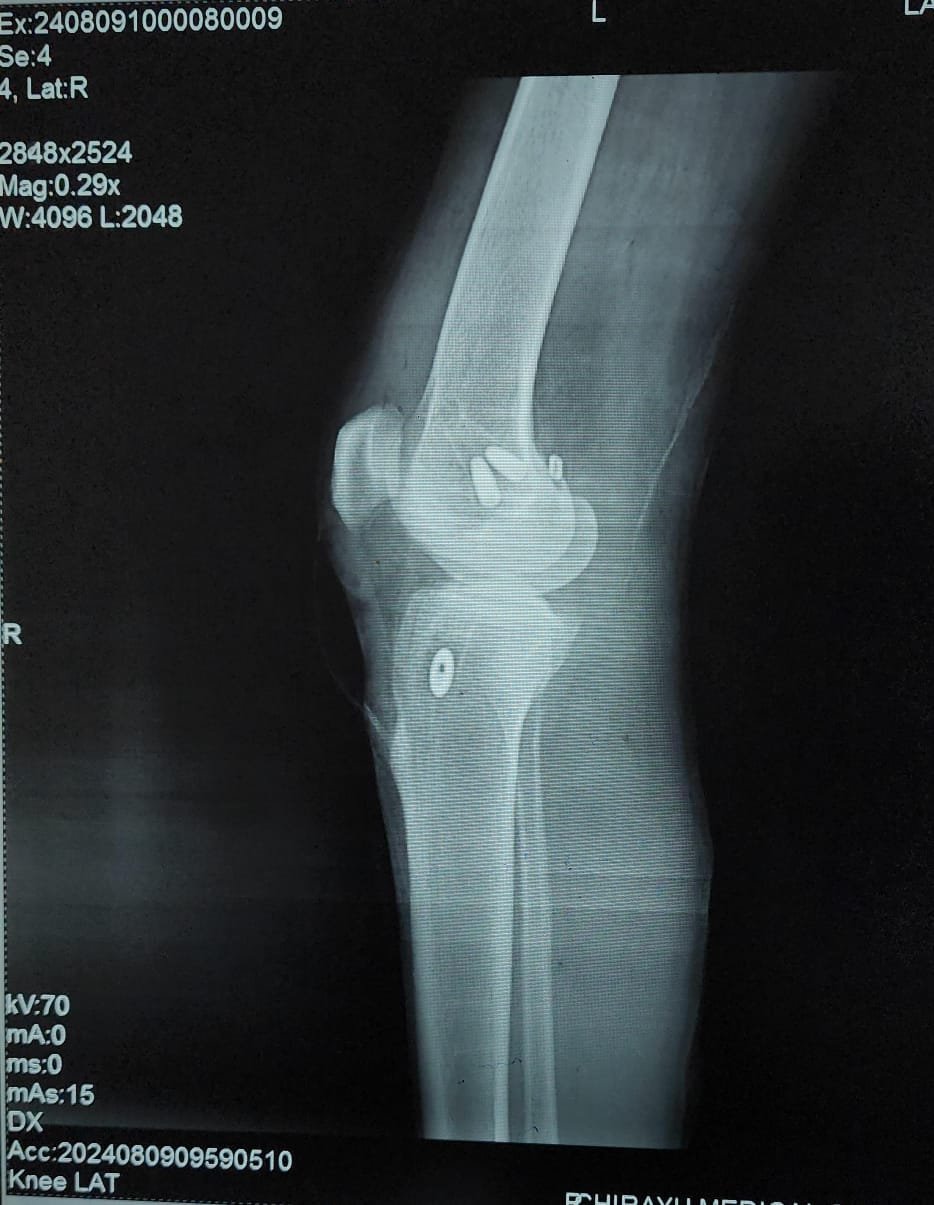

- Knee Replacement Surgery